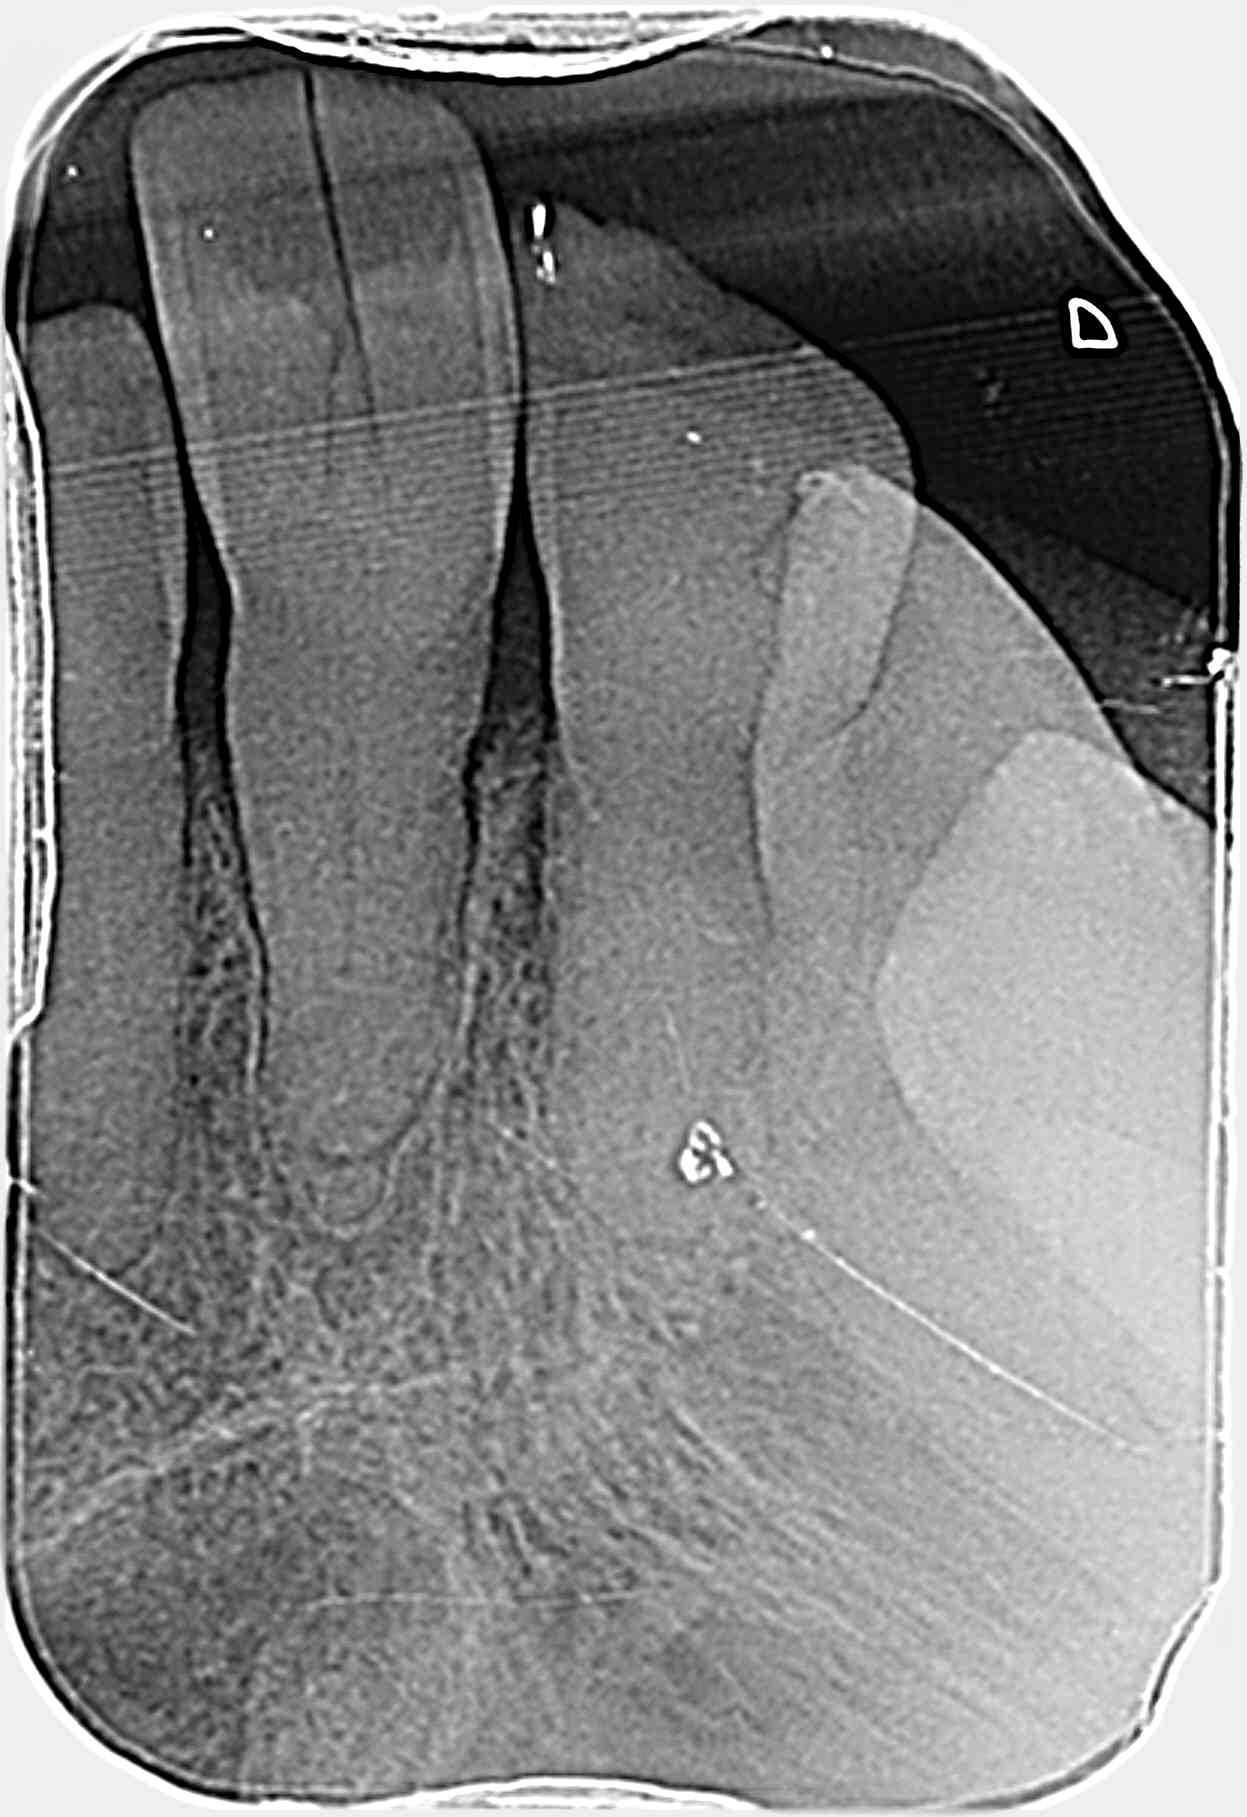

Bonjour, je vois une patiente, dans le cadre d'un bilan, de 88 ans en pleine santé une 1ère fois avec une 21, cl2.1, qui présente une fissure.

J'ai effectué la radio par curiosité

Le seul défaut, une classe 2.1, avec contact des mandibulaires à la base radiculaire des centrales, des racines lustrées par des facettes légères d usure des incisives mandibulaires, donc perte osseuse en palatin avec un niveau normal en vestibulaire.

Une facette creusée d usure sur la 21.